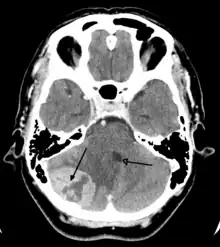

A tumor of the posterior fossa leading to mass effect and shift of the fourth ventricle- Video (44 sec). Demonstrationg how cerebellum sits in the posterior cranial fossa.